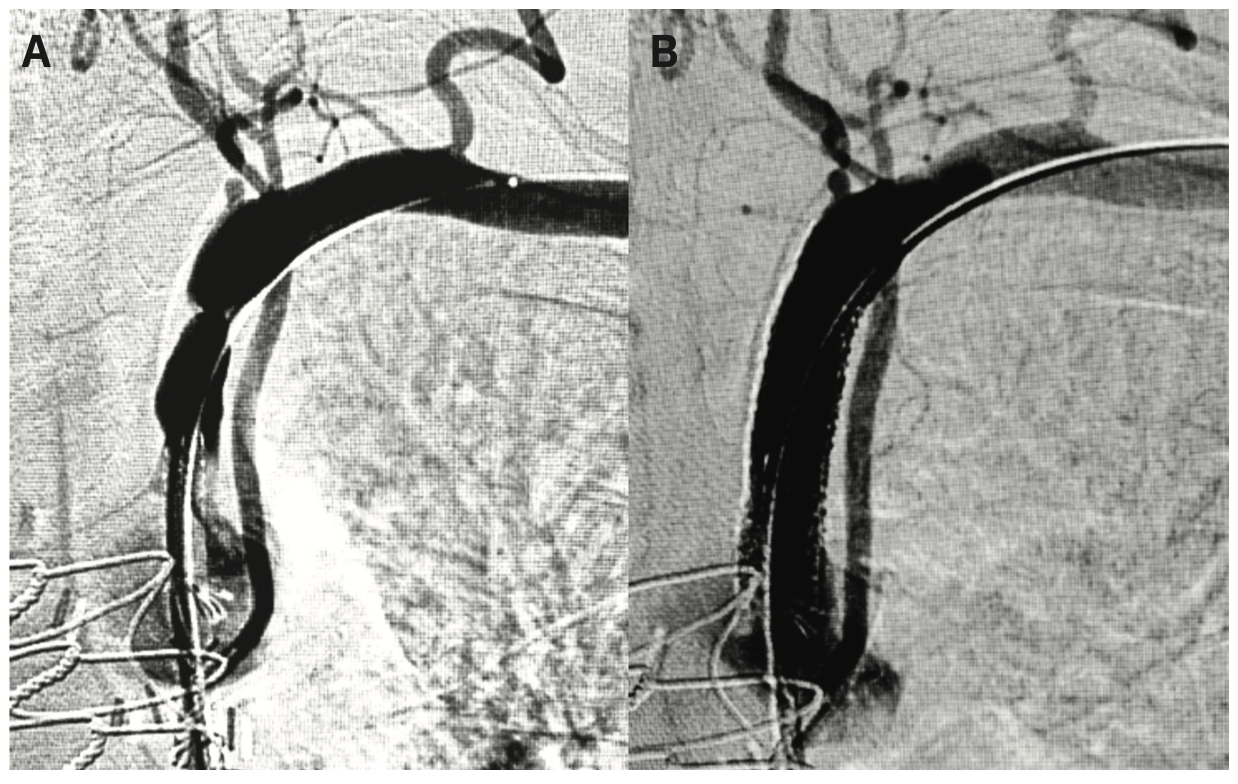

Several weeks after the endovascular interventions, the patient’s claudication significantly improved to the point that they were able to walk without leg pain. However, the patient now developed typical exertional angina. They were admitted, and underwent coronary and graft angiography, demonstrating an 80% stenosis of the proximal left subclavian artery with >90 mmHg pressure gradient on pullback, resulting in coronary steal of blood flow from the left internal mammary artery (LIMA) graft to the left anterior descending (LAD) coronary artery (Figure 3A). As this was not the site of prior access (the endovascular interventions were performed through right radial approach), it was believed to be a chronic stenosis with anginal symptoms now unmasked after improvement in claudication and exertional capacity. The lesion was stented with an 8 mm x 37 mm Express LD (Medtronic) bare-metal stent (Figure 3B), with complete resolution of angina on follow-up.